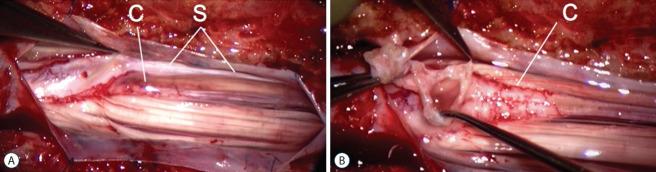

Spinal dysraphic lesions due to focal nondisjunction in primary neurulation are commonly encountered in paediatric neurosurgery, but the "fog-of-war" on these conditions was only gradually dispersed in the past 10 years by the works of the groups led by the senior author and Prof. Kyu-Chang Wang. It is now clear that limited dorsal myeloschisis and congenital spinal dermal sinus tract are conditions at the two ends of a spectrum; and mixed lesions of them with various configurations exist. This review article summarizes the current understanding of these conditions' embryogenetic mechanisms, pathological anatomy and clinical manifestations, and their management strategy and surgical techniques.

由于原发性神经管形成过程中的局灶性不分离导致的脊柱裂病变在小儿神经外科中很常见,但在过去10年中,由资深作者和王宇辰教授领导的团队的工作才逐渐驱散了这些病症上的“战争迷雾”。现在已经明确,有限性背侧脊髓裂和先天性脊柱皮样窦道是同一谱系两端的病症;并且存在各种形态的它们的混合病变。这篇综述文章总结了目前对这些病症的胚胎发生机制、病理解剖和临床表现,以及它们的治疗策略和手术技术的认识。